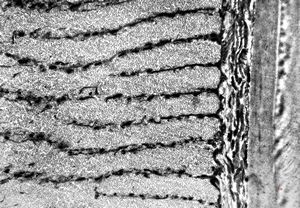

Oxyuris vermicularis - muscular wall